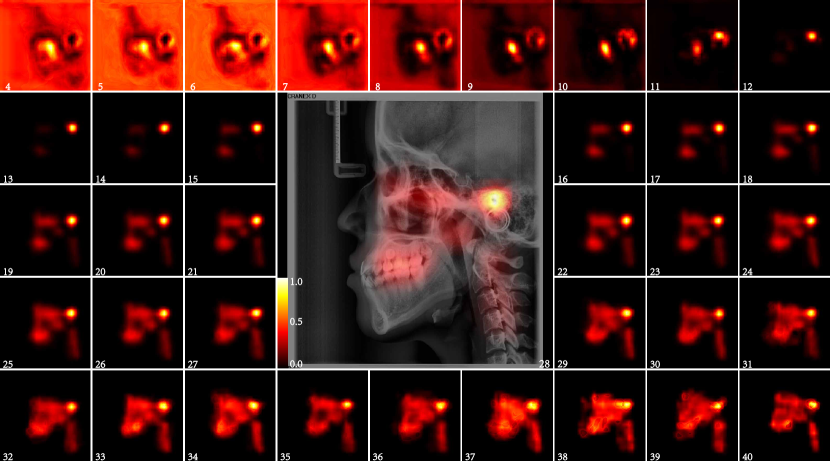

The average saliency maps of each part were shown in Fig. 12, Fig.13 and Fig.14. The salient area of each part is consistent with that of the whole LC image. The location and shape of the salient area in the heat map of each year age group showed a high degree of consistency. The salient area of teeth part were mainly teeth and periodontal tissues, especially the upper posterior teeth, this should be related to the wear of the teeth and the ageing changes of the periodontal tissue.(Fig. 12) The salient area of the craniofacial part without the teeth were mainly midface(Fig.13). Many scholars have conducted in-depth research on the aging changes of the orbit, and the volume of the orbit increases with age. The development of the maxilla is also a research hotspot, but the research on the aging of the maxilla in adults has not been involved. The saliency maps reminds us that it is necessary to conduct aging research on other organizational structures in the middle of the face. The salient area of the cervical spine part were all of cervical spines and intervertebral disc in the LC image. The morphological changes of the cervical spine are used to determining the pubertal growth spurt of adolescence[27-29]. The cervical spine was also used to infer age and gender [30-32] , but it is mainly used for children and adolescents, there is no relevant research using the cervical spine to infer the age of adults. The cervical spine consists of 7 vertebral bodies and intervertebral discs. After the development is complete, the structural changes of the cervical spine begin in middle age, but sometimes earlier[33]. I ntervertebral disc degeneration begins at adolescence, and as it progresses, it can also leads to morphological alterations of the vertebral bodies. Cervical lordosis increased with age[34]. These changes are difficult to use by traditional methods of inferring age.

In this study, we found that the accuracy of age estimation of cervical part is the highest among all parts in the 26-40 age group, which indicates that cervical region should be highly concerned, which is worthy of further study.